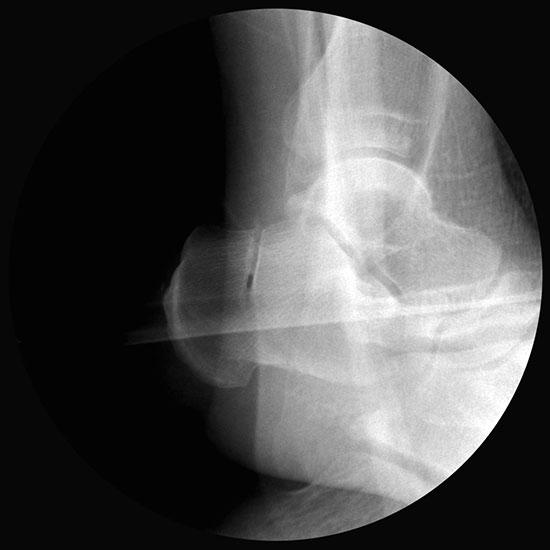

Operationsplanung anhand der Röntgenaufnahmen unter Beachtung wichtiger radiologischer Landmarks wie Rückfussachse, Metatarsale I – Talushals-Achse im dp und lateralen Strahlengang (Abbildung 1 und 2).

Abbildung 1

Abbildung 2